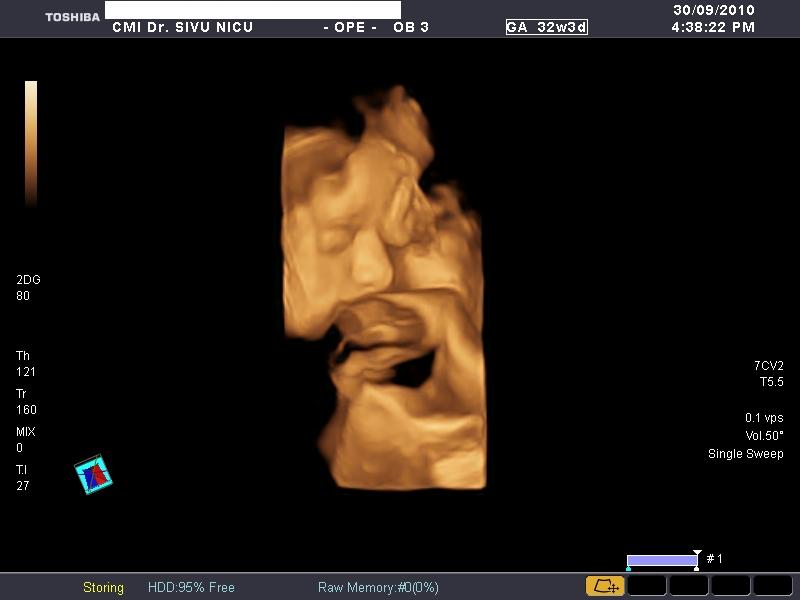

De sarcina (morfologie,biometrie,3D si 4D)

Poze realizate pe ecograful

Toshiba Applio XG